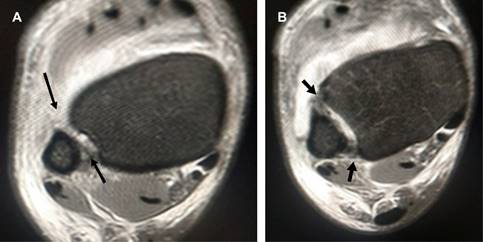

Masculino de 25 años que tres semanas atrás sufrió inversión del tobillo derecho durante la marcha, se automanejó con férula AeroCast por dos semanas, permaneciendo asintomático por tres días en que inició trote de 5 km, presentando al final dolor intenso y edema de cara anterior de tobillo. A la exploración dirigida: edema de la zona, dolor intenso durante pruebas de Hopkinson y de estrés en rotación externa del pie, por lo que con diagnóstico de lesión de la sindesmosis tibioperonea inferior se solicitan radiografías (Figura 1A y B) y resonancia magnética (Figura 2), confirmando diagnóstico. Se efectuó fijación de la sindesmosis con el sistema TightRope, que ancla los extremos de la tibia y el peroné mediante un cordón de polietileno trenzado (Figura 1C) y reconstrucción de la cápsula articular. Se colocó inmovilizador de tobillo y se canalizó a las tres semanas a rehabilitación.

Figura 2: Imágenes de resonancia magnética en cortes axiales de tobillo, ponderadas en T2 que muestran ruptura de los ligamentos tibioperoneos anterior, posterior e interóseo (flechas negras) y líquido intraarticular con diástasis de la sindesmosis.